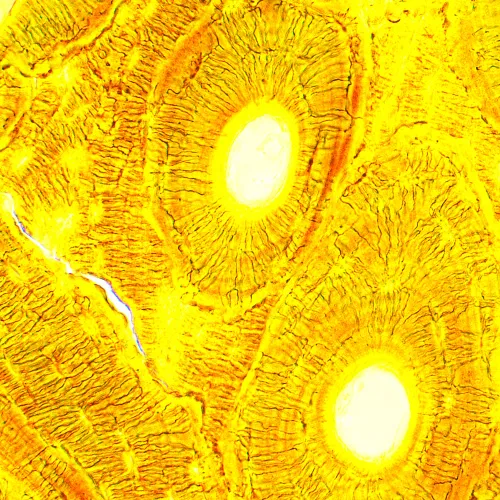

Il microscopio biologico MAGUS Bio 230B è uno strumento professionale per l’osservazione di campioni biologici in luce trasmessa. La principale tecnica di microscopia usata è quella in campo chiaro (immediatamente accessibile). È possibile usare anche tecniche di osservazione in campo oscuro, con contrasto di fase o luce polarizzata, ma richiedono l’impiego di accessori da aggiungere al microscopio. Questo microscopio è perfetto per le osservazioni in laboratorio e per la ricerca in campo medico, farmaceutico, forense, agricolo e vari altri campi.

Gli obiettivi planacromatici forniscono immagini chiare, ricche di contrasto e di dettagli con aberrazioni minime. L’ingrandimento, usando degli obiettivi e degli oculari inclusi nella confezione, varia da 40x a 1000x, ma il limite superiore può essere aumentato con l’uso di oculari aggiuntivi. Le ottiche sono corrette all’infinito, il che significa che vari altri accessori possono essere inseriti lungo il cammino ottico.